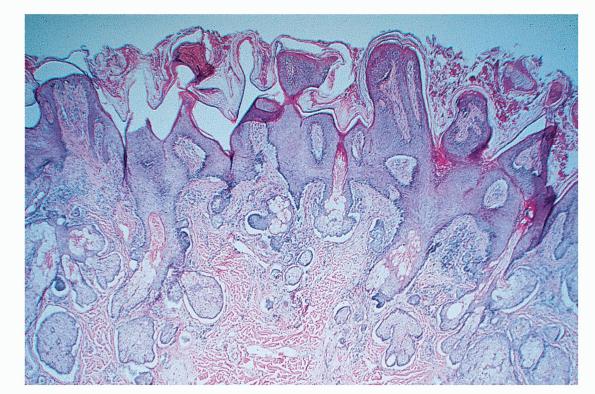

Nevus_sebaceous = الوحمة الدهنية